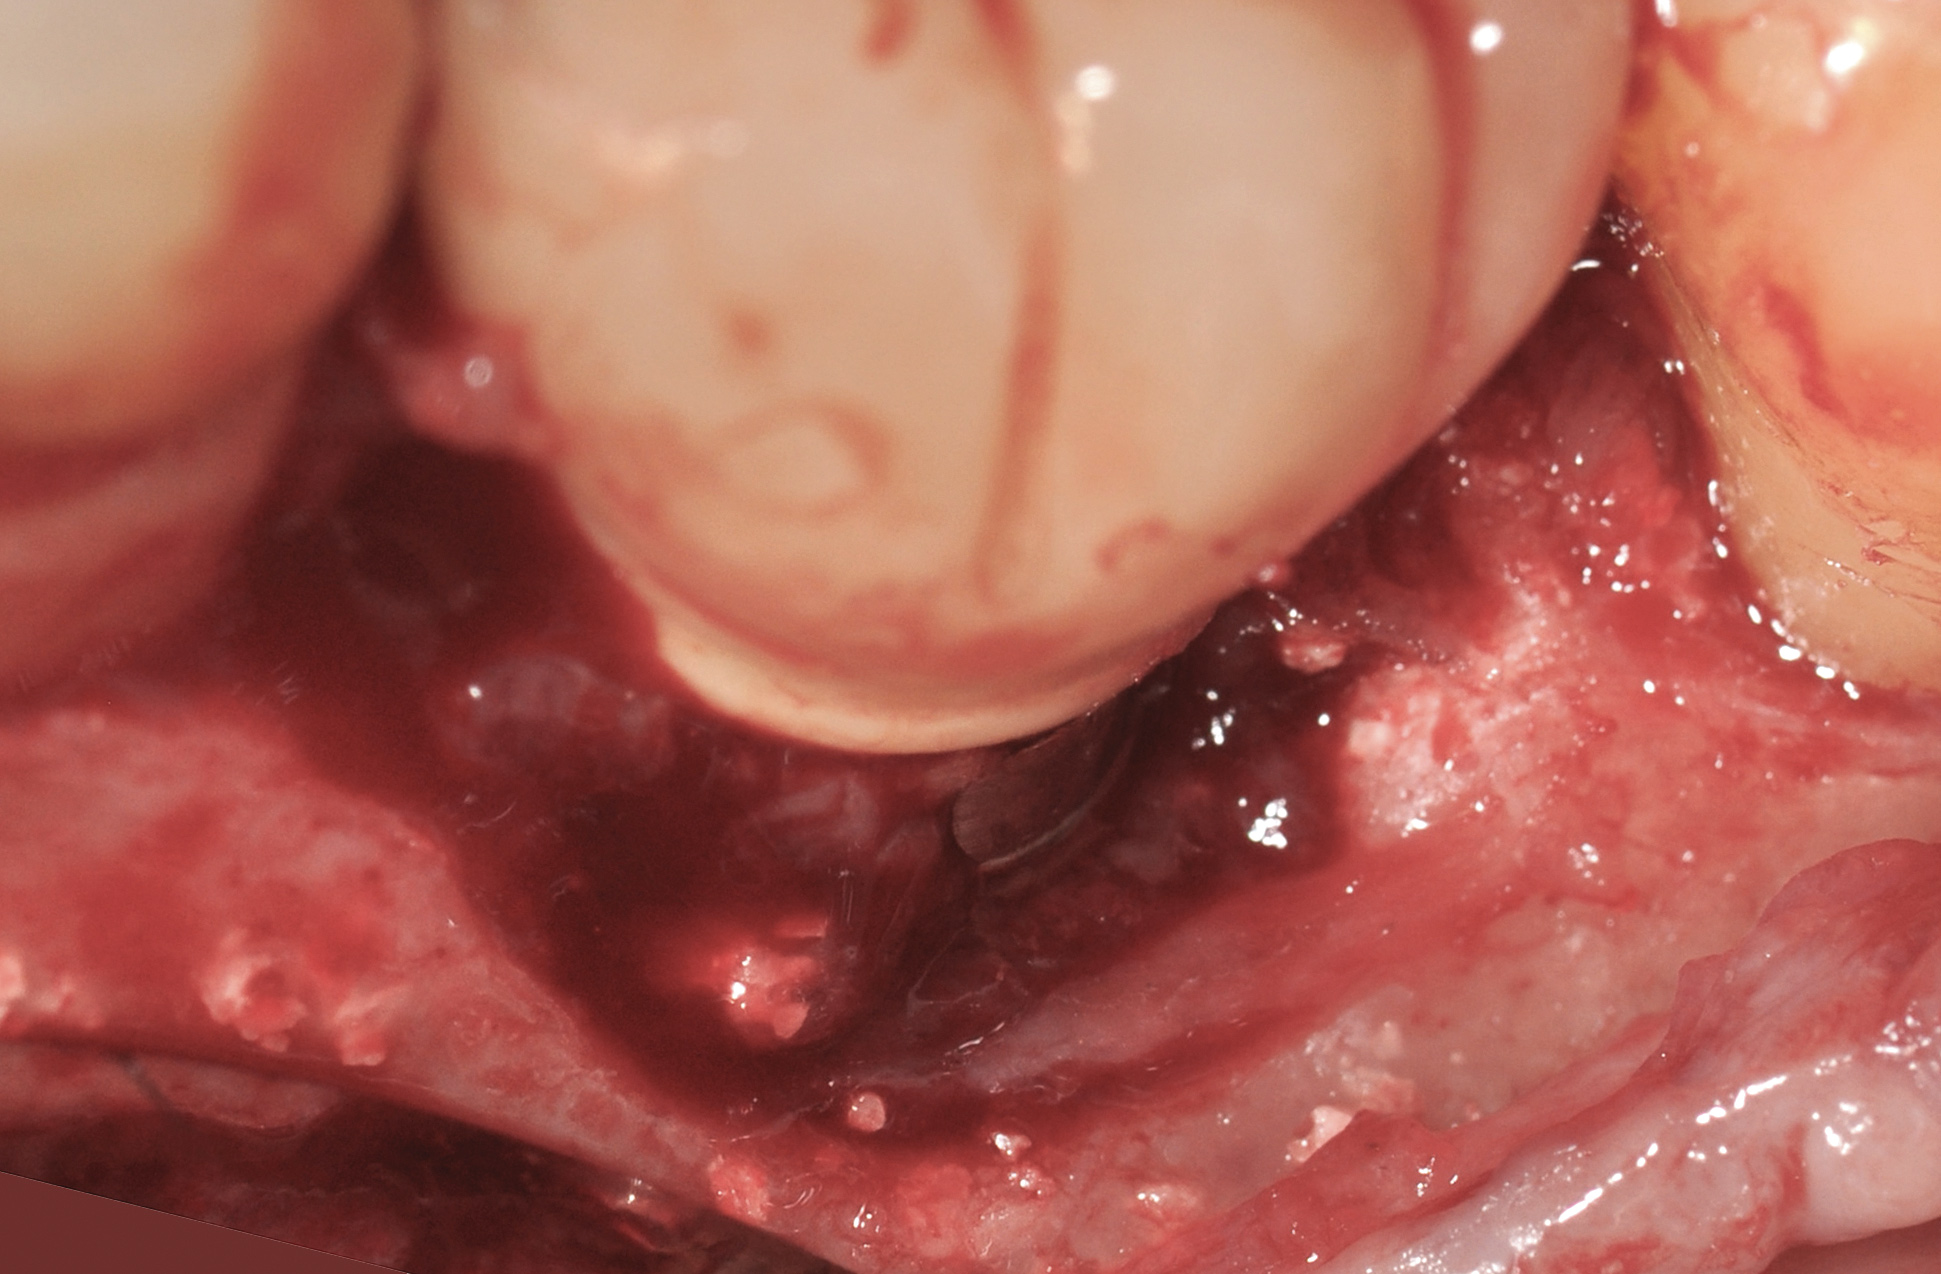

Fig 18. A full-thickness flap from teeth Nos. 18 to 20 revealed granulomatous tissue in the circumferential defect around implant No. 19.

Figure 18

Fig 19. The circumferential defect was debrided. Note excess cement extending apically from the margin of the crown into the defect; residual cement has been shown to be complicit in the development of peri-implant disease.

Figure 19